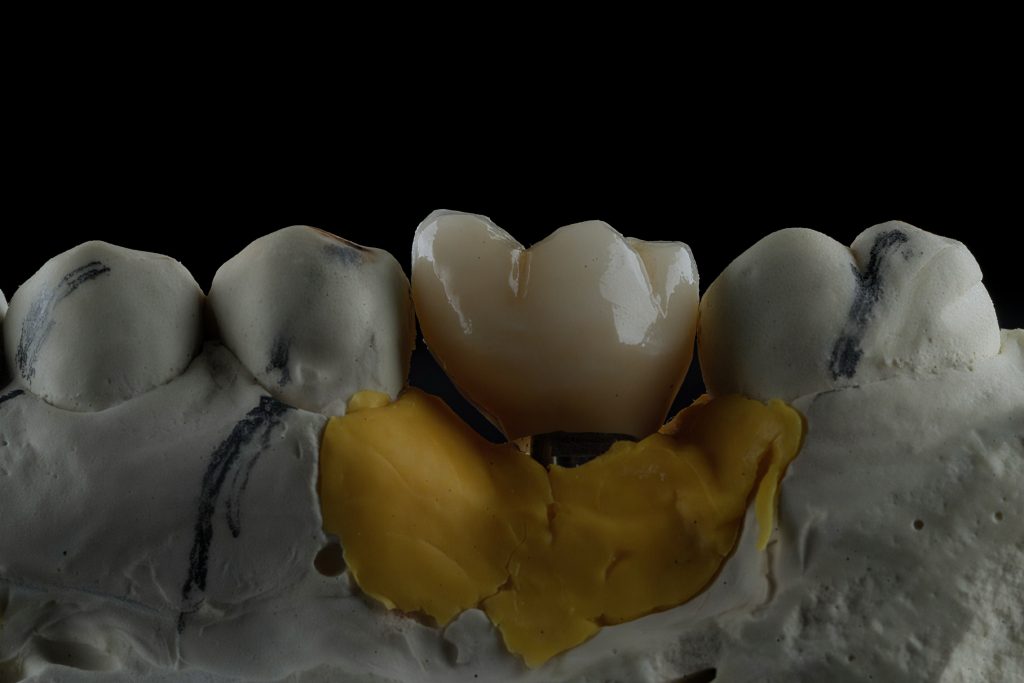

A precision-milled titanium base abutment was torqued to the manufacturer’s specification. The abutment contour was selected to promote a natural gingival transition and preserve the mucosal seal.

3. Crown Fabrication

A monolithic zirconia prosthesis was fabricated with precise occlusal morphology and central screw access for retrievability. The restoration was individually characterised and glazed to reproduce enamel texture and hue harmony with adjacent teeth.

4️⃣ Monolithic zirconia crown on master model